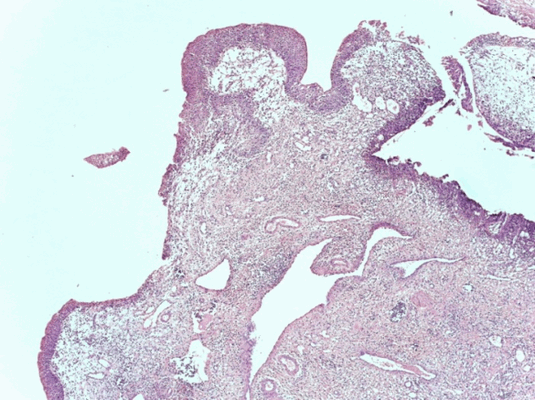

Патоморфологическое исследование пациента С.

Морфологическая картина полипоидного цистита. Окраска гематоксилин-эозином, х5

Патоморфологическое исследование пациентки К.